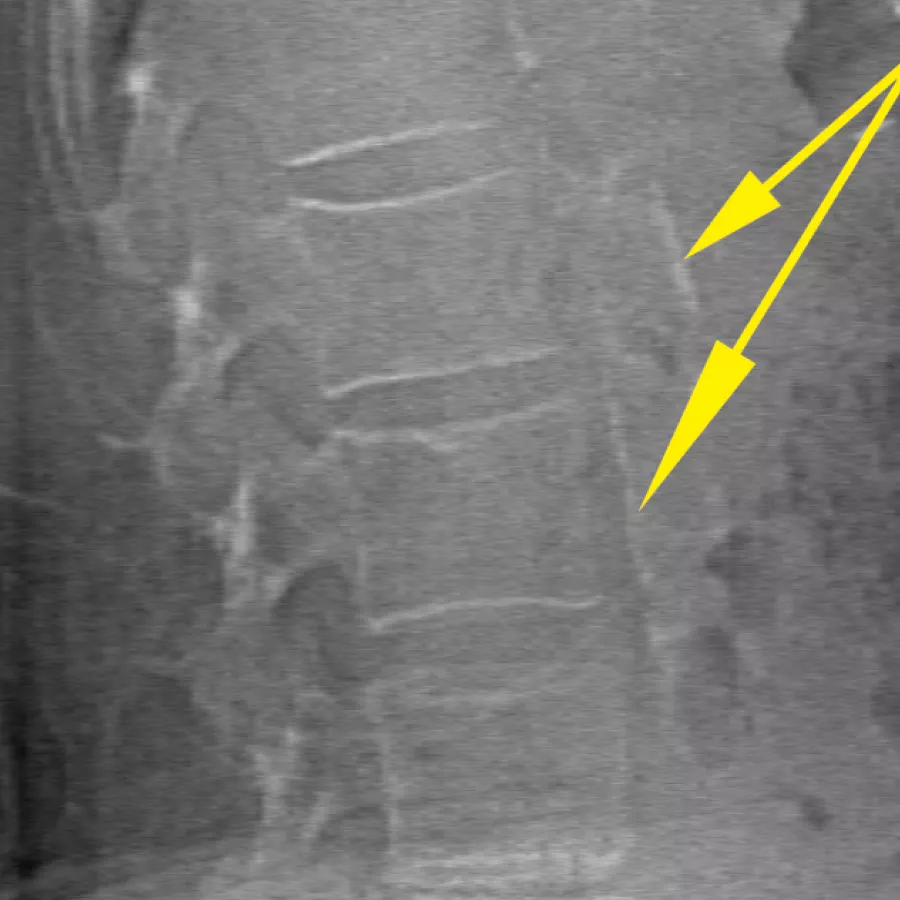

Horizon DXA produces radiographic quality images of the entire femur for assessment of potential atypical femur fractures.31 A quick, 15-second scan reveals cortical thickening of the bone, making it fast and easy to monitor the effects of bisphosphonate therapy over time.

Assess fracture risk by combining an accurate measurement of bone density with high-resolution vertebral imaging. You can identify spine fractures with a low-dose, single-energy image in 10 seconds.

Improve accuracy and reduce post-exam analysis errors with precise, software-assisted placement of inter-vertebral disc spaces for graphic analysis.